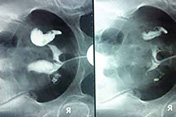

“四镜一丝”联合复通术能保护输卵管绒毛蠕动功能的输卵管疏通技术,超导可视真正不伤输卵管,而非单单疏通输卵管。

宫腹腔镜技术,将0.38毫米的导丝通过腔道送入阻塞部位,直接疏通输卵管堵塞,对人体造成损伤小。

检查、疏通、治疗同步完成,在直接疏通堵塞的同时,注入防粘连药物,避免传统通气、通水、通药带来的痛苦和反复拈连等问题。